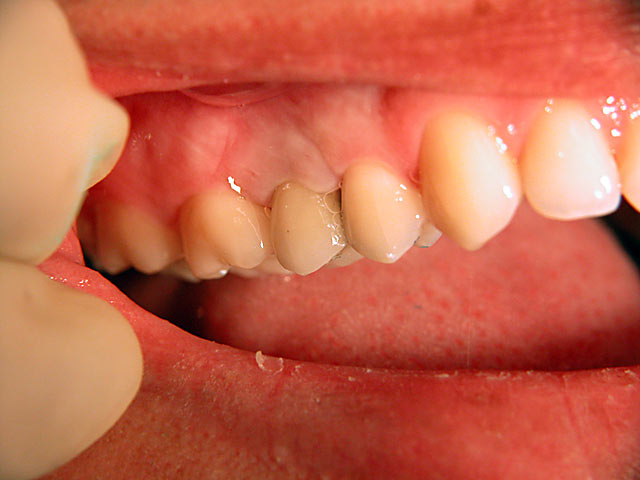

Frontzahn-Implantation: